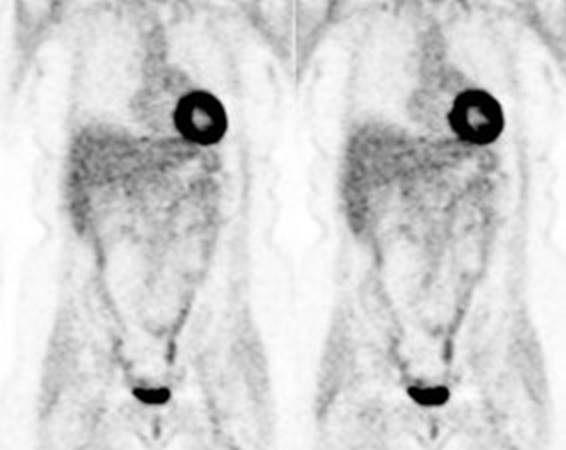

Figure 11 - Brown Fat: Prominent, symmetric

supraclavicular tracer uptake was seen in this patient without a corresponding

CT finding. Uptake in this area has been felt to be related to the presence of

"brown" fat.